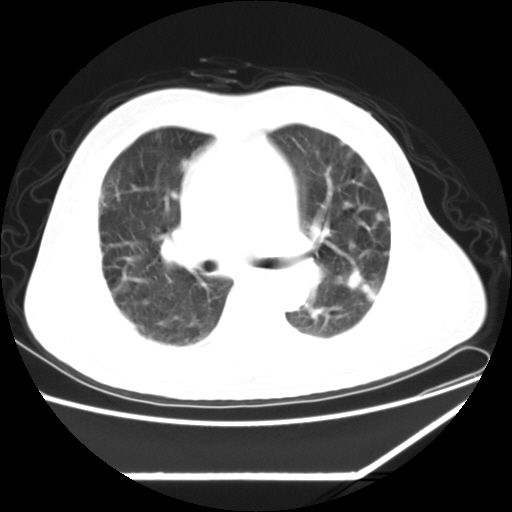

男,57,畏寒,发热

双肺多发结节样病灶,部分内见透光区,纵隔内见淋巴结肿大。结核临床如有畏寒,高热,白细胞增高首先考虑迁徙性肺脓肿(多是金黄色葡萄球菌感染)。

注意除外转移瘤。

双肺典型的亚急性粟粒性肺结核

双侧胸膜结核